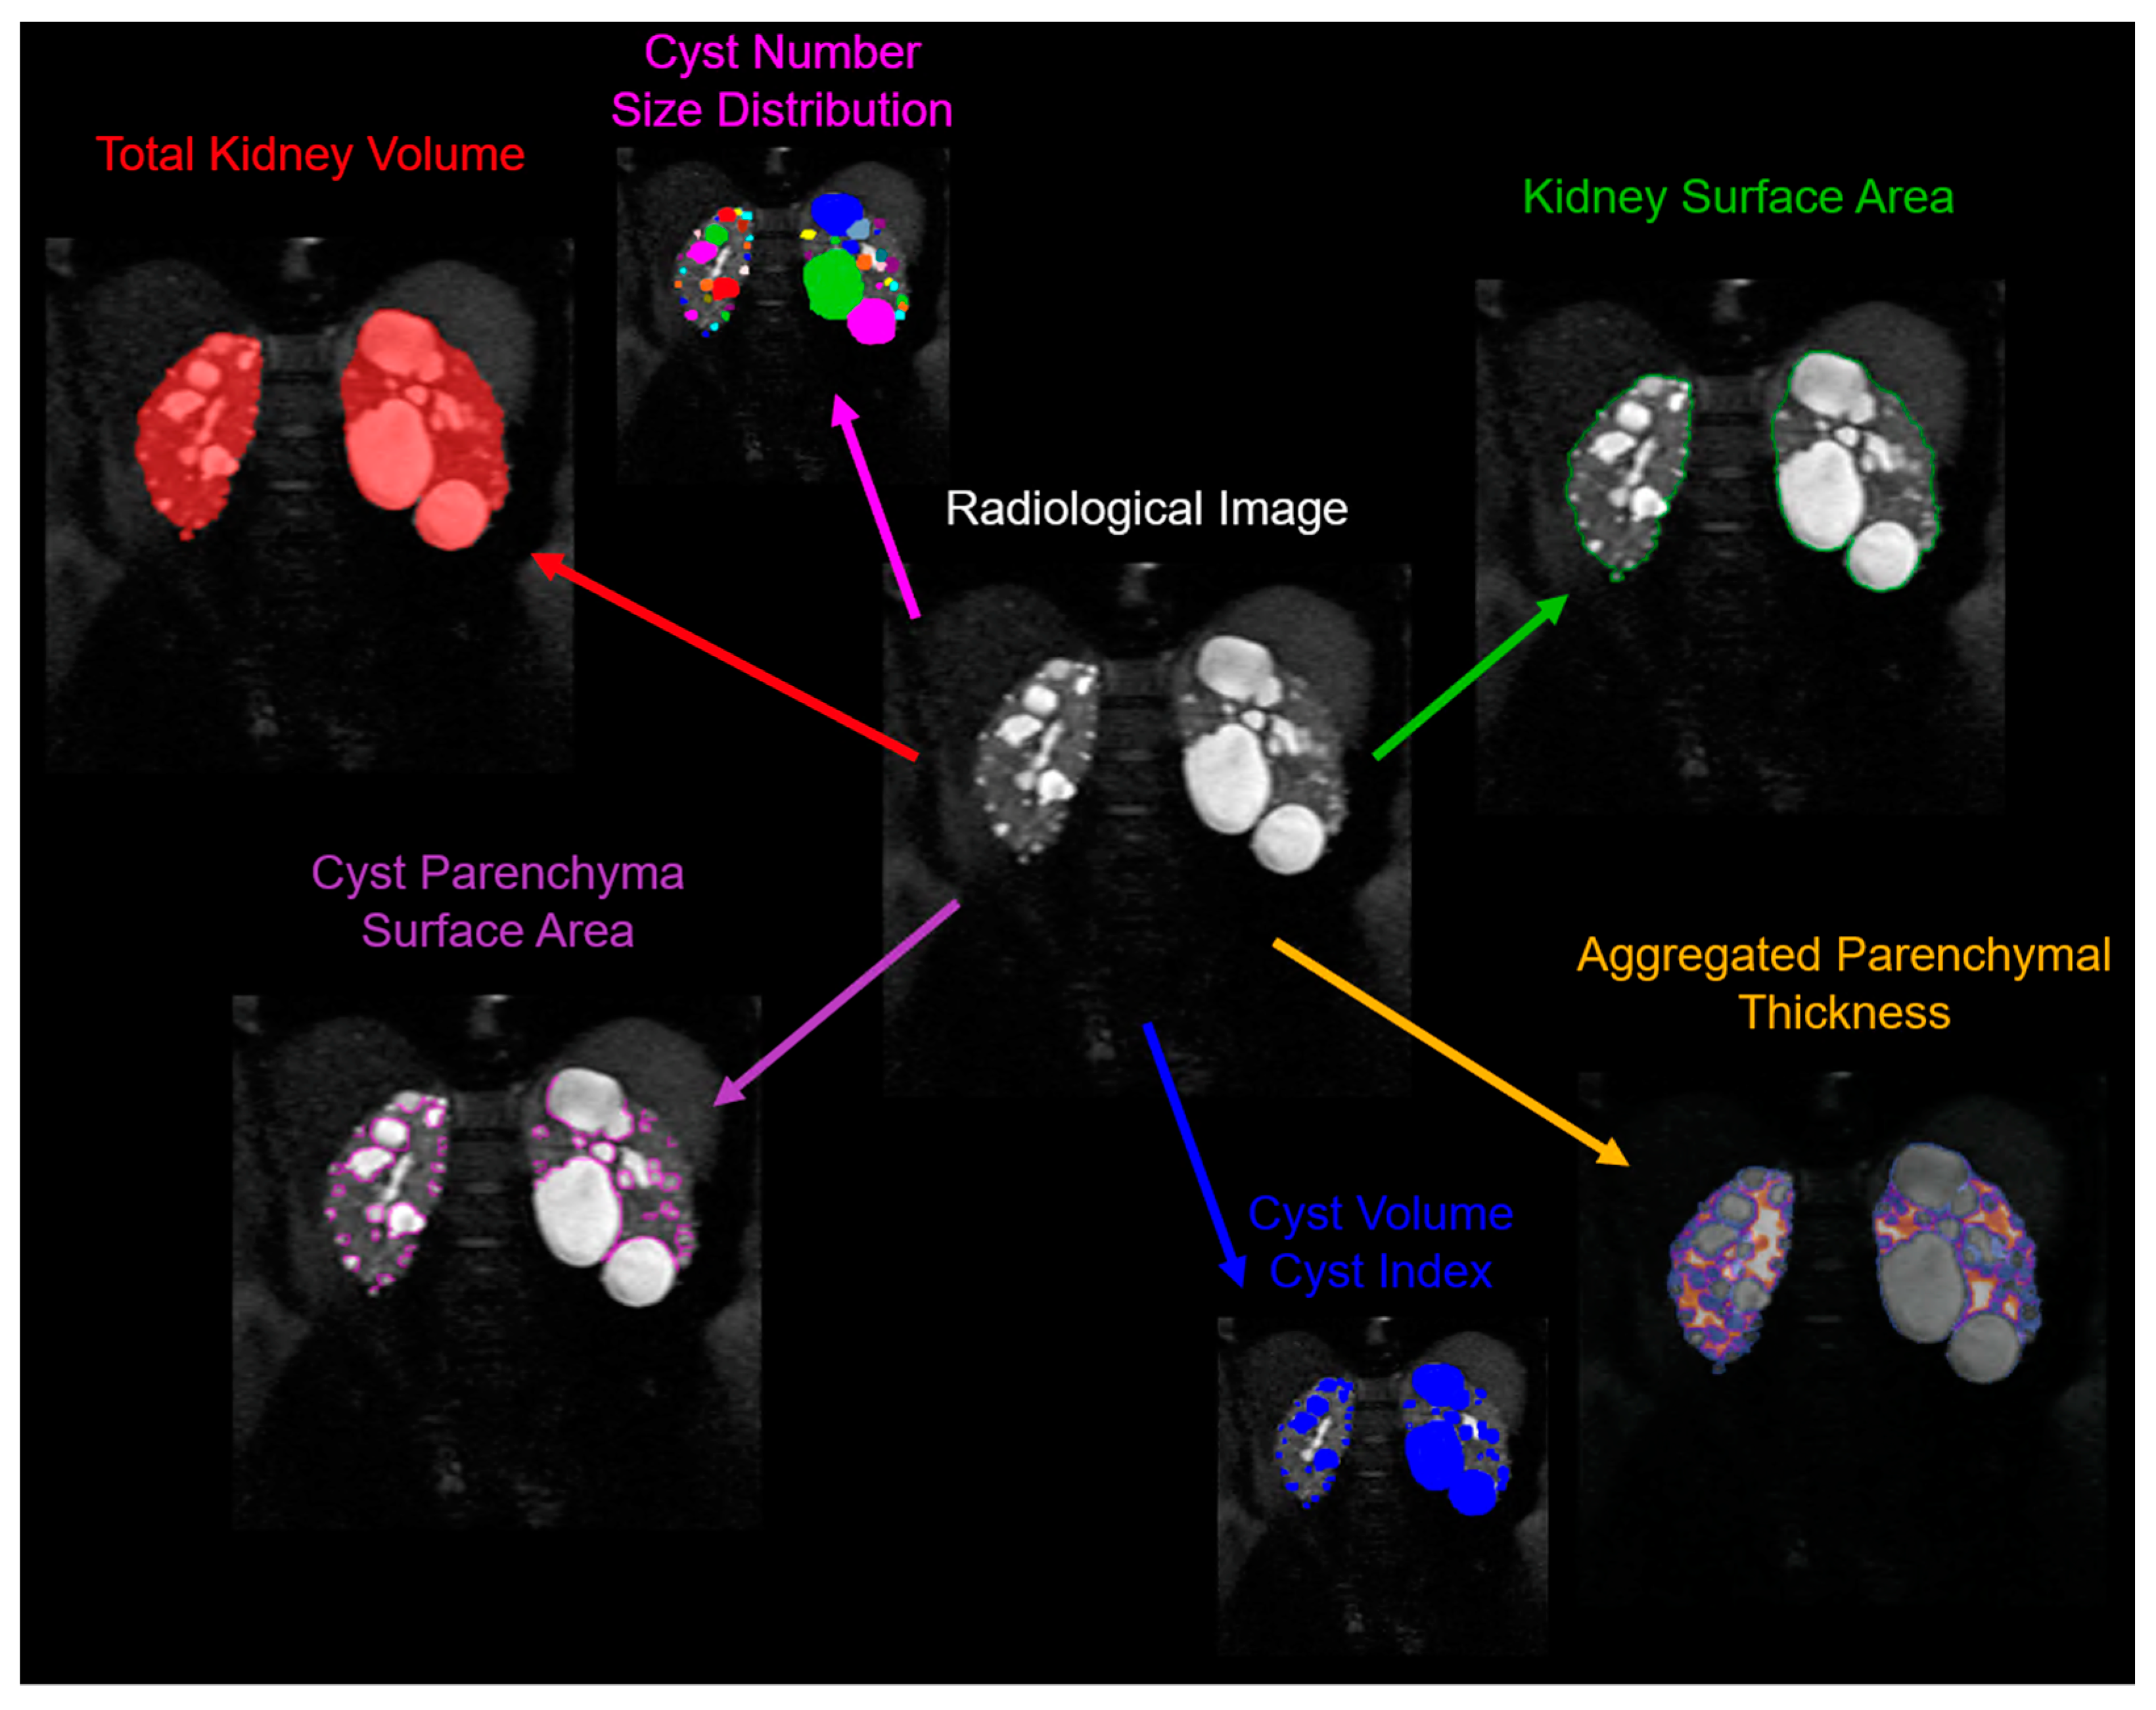

Although the TKV, which includes both cystic and non-cystic components, has been identified as a reliable biomarker of disease progression, the assessment of the cyst burden by itself is likely a more detailed characterization of the state of disease (Figure 3). Several studies have shown a strong correlation between cyst volumes and ADPKD progression.

Figure 3.

Example of a multifaceted analysis of ADPKD pathology derived from a single radiological image. This representative image depicts the comprehensive measurement parameters that can be employed to provide in-depth information about kidney enlargement and the cyst burden in ADPKD. Clearly delineated are various parameters, including: the total kidney volume—indicating the comprehensive volume of the kidney, inclusive of cysts and the parenchyma; the cyst number and size distribution—signifying the count and varying dimensions of individual cysts present in the kidney; the kidney surface area—the measure of the external boundary of the kidney; the aggregated parenchymal thickness—denoting the cumulative thickness of the renal parenchyma; the cyst volume—indicating the space occupied by each individual cyst; the cyst index—a ratio demonstrating the proportion of the kidney volume taken up by cysts; and the cyst parenchyma surface area—representing the interface between the cystic and non-cystic renal tissue. This multiparametric assessment provides a granular view of the ADPKD-affected kidney, which aids in understanding disease progression, and may guide clinical decision making and therapeutic decisions.